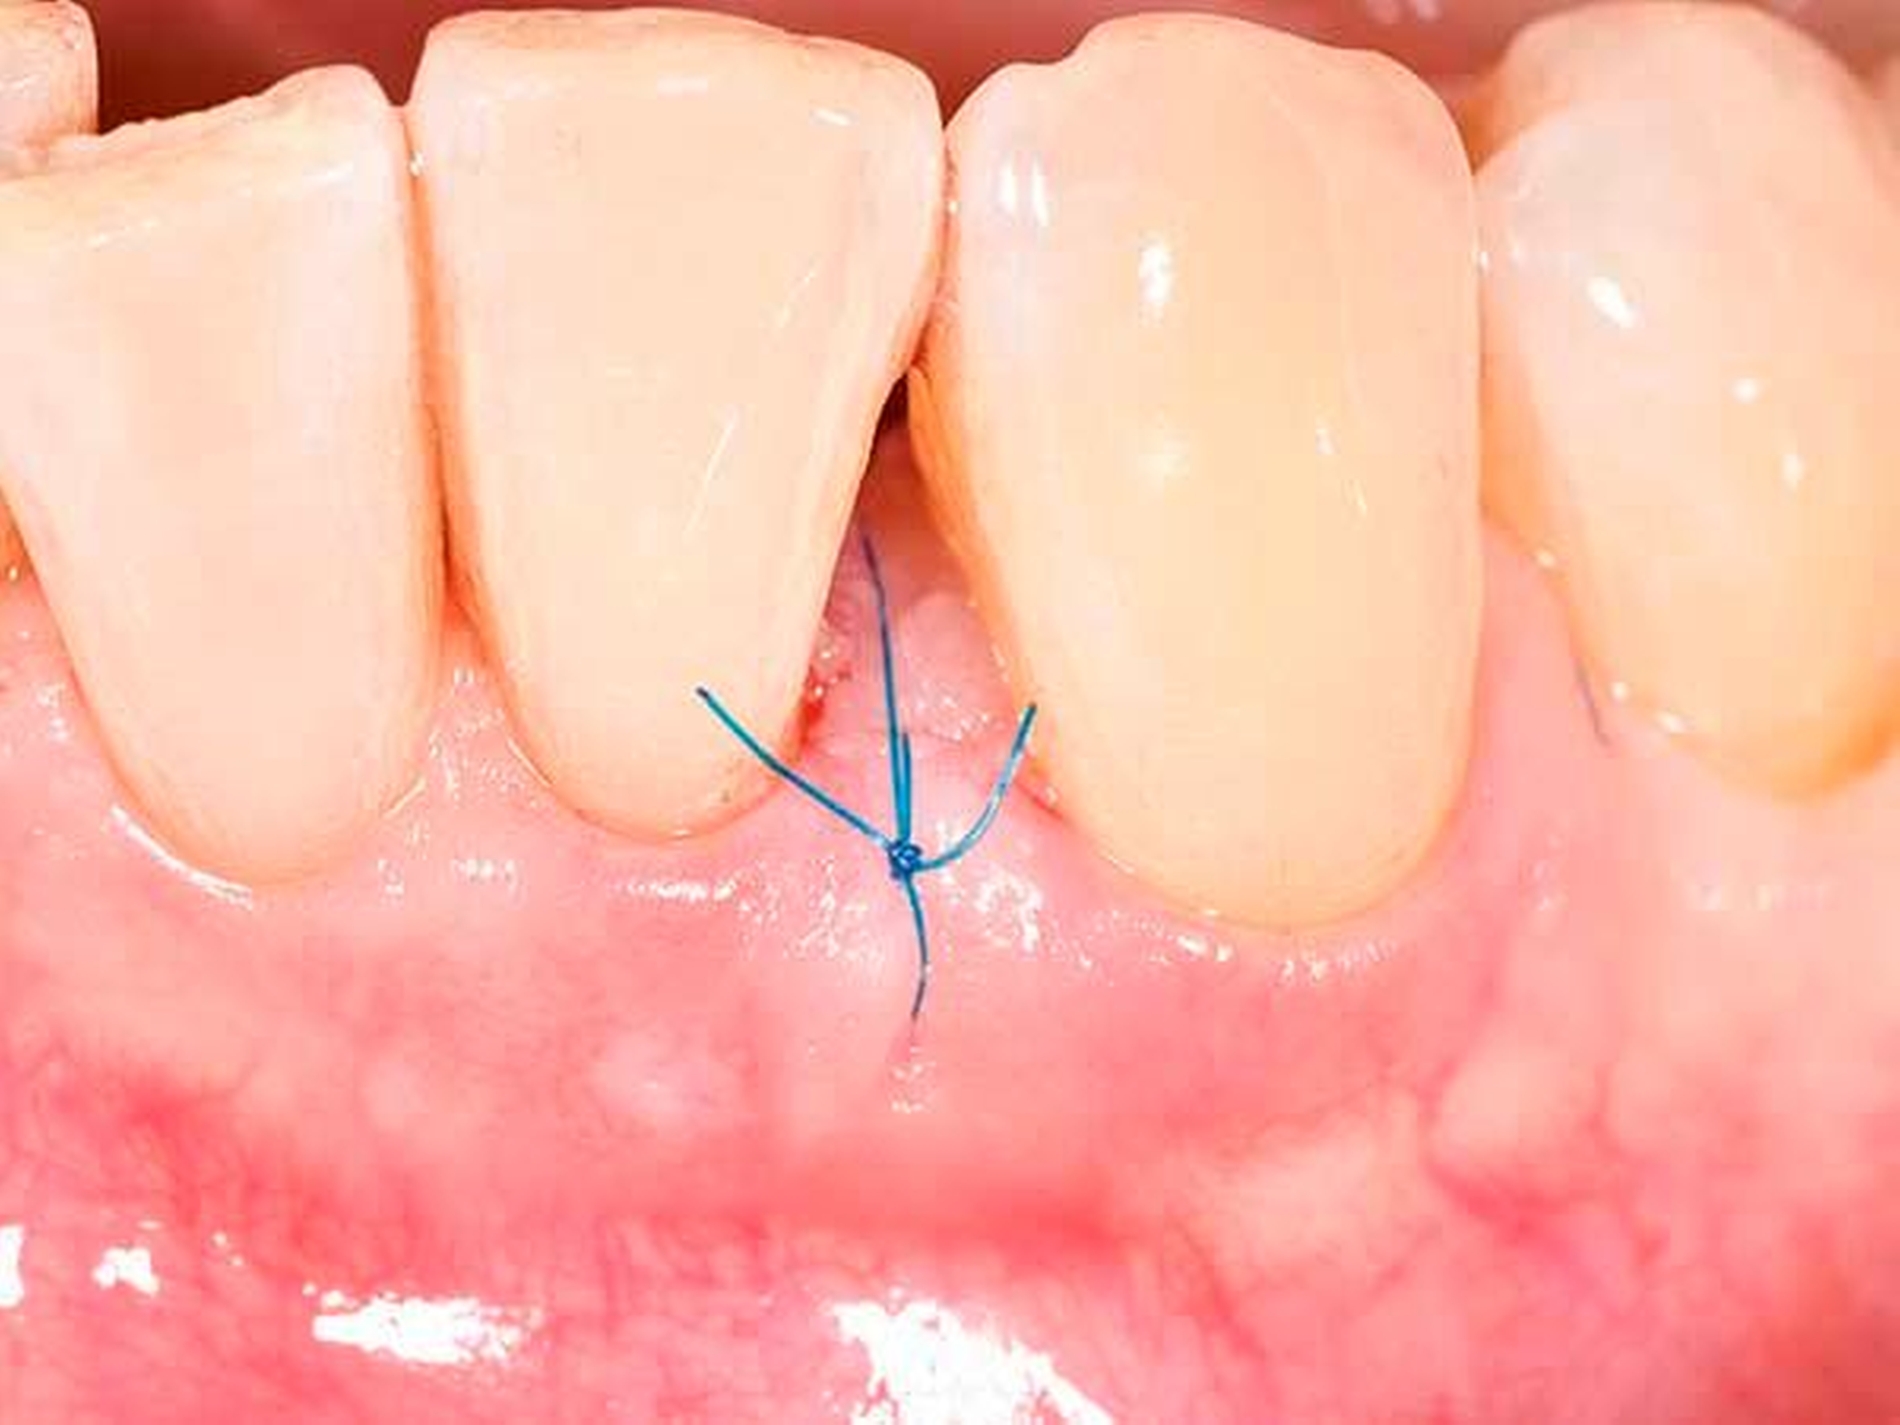

Es ist nachvollziehbar, dass eine solche Modifizierung der parodontalen Wundheilung nur Berücksichtigung von systemischen und lokalen Patientenfaktoren sowie einer optimalen chirurgischen Technik funktionieren kann. Als wesentlich hat sich auf Ebene der Patientenfaktoren herausgestellt, dass regenerative Eingriffe bei Patienten mit Vorliegen von Verhaltensfaktoren wie Rauchen oder mangelnder Compliance sowie von systemischen Faktoren wie einem schlecht eingestellten Diabetes mellitus oder einer hohen Stressbelastung mit einem deutlich erhöhten Misserfolgsrisiko vergesellschaftet sind. Auf lokaler Ebene ist zu fordern, dass der zu regenerierende Defekt eine möglichst große Tiefe sowie einen möglichst geringen Defektwinkel aufweisen sollte (Abbildung 6a). Mehr als die Hälfte der Variabilität eines regenerativen parodontalchirurgischen Eingriffs konnte in einer klassischen Studie auf die Kombination der Faktoren Defekttiefe und Defektwinkel zurückgeführt werden [Tonetti et al., 1996]. In einer deutschen Studie wurde erst bei Defekten einer intraossären Tiefe von 3 mm oder mehr sowie eines Defektwinkels von 25° und weniger ein deutlicher Attachmentgewinn nachgewiesen [Klein et al., 2001]. Zusätzlich erfordert ein regenerativer Eingriff optimierte Weichgewebeverhältnisse (Abbildung 6b) – die Zahl von parodontalpathogenen Bakterien des roten Komplexes ist direkt mit einer verschlechterten OP-Prognose assoziiert [Heitz-Mayfield et al., 2006], und die Möglichkeit eines primären Verschlusses der Lappen ist ein wesentlicher Faktor für den Erfolg des regenerativen Eingriffs [Cortellini und Tonetti, 2015]. Zur Sicherstellung der primären Deckung des OP-Gebiets sind verschiedene papillenerhaltende Lappentechniken beschrieben worden. Häufig werden in Abhängigkeit von der Breite der Interdentalpapille der modifizierte (Abbildung 7a bei dreiwändigen Defekten wie in Abbildung 7b; Abbildung 7c bei ein- oder zweiwändigen Defekten wie in Abbildung 7 d) oder der vereinfachte Papillenerhaltungslappen (Abbildungen 7e und 7f) angewendet.